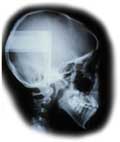

骨の形は側面セファログラムというレントゲンによって、把握する事ができます。

骨の上にのっている軟組織の形と骨との関係を、側面セファログラムでは把握することができます